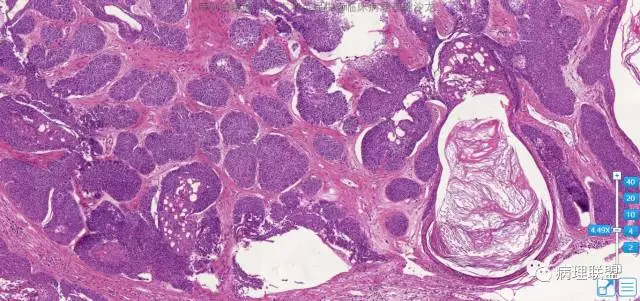

病例4

女,62,左面部

图片信息

@左淑英 1毛囊瘤,2毛发上皮瘤。3是钙化上皮瘤。4是外毛根鞘瘤

四个病例,有点混乱了。3钙化上皮瘤。4增生性外毛根鞘瘤,2毛母细胞瘤,1分不清了毛囊分化,请左老师有时间讲解一下